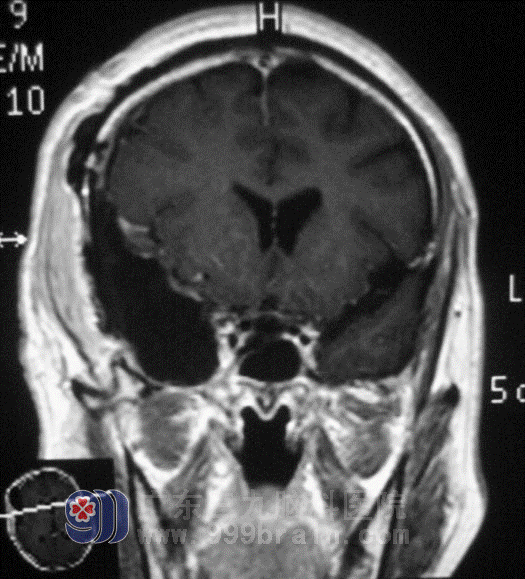

Within complete checking before operation, on May 19, Lu Ming Director carried out the operation that he cut off right lobus temporalis for Mr. Liu. Lu Ming Director dealt with the operation steadily and completed the hard operation successfully. Mr. Liu entered recovery stage smoothly, by being in the hospital to treat, Mr. Liu had not any other diseases to happen and he turned to Radiotherapy Department for further treatment.

after operation